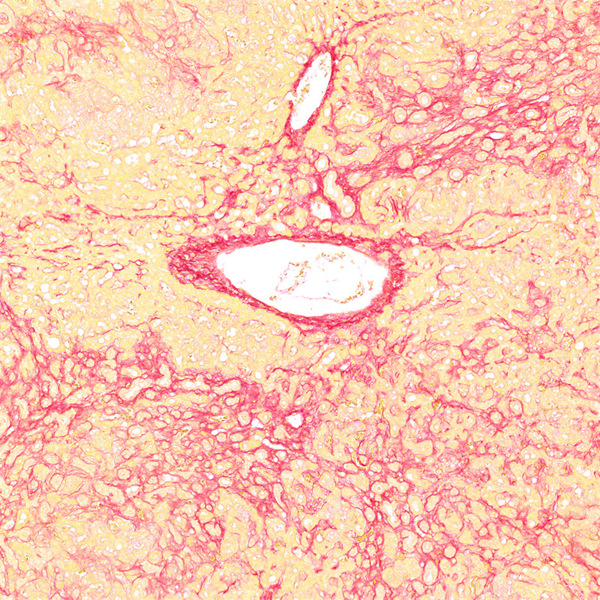

天狼猩红和KWS都是强酸性染料,易与胶原分子中的碱性基团结合,吸附牢固。偏振光镜检查,胶原纤维有正的单轴双折射光的属性,与KWS-天狼猩红结合,可增强双折射,提高分辨率,从而区分两型胶原纤维。未脱钙骨组织切片经天狼猩红染色后,普通光学显微镜下,胶原纤维呈红色或鲜红色,其他呈黄色;在偏振光显微镜下,Ⅰ型胶原纤维呈强橙黄色或亮红色,Ⅲ型胶原纤维呈绿色。

实验结果展示:

天狼星红-肝>